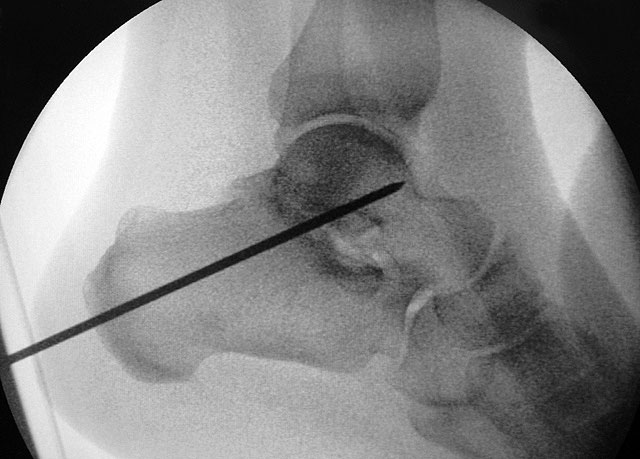

Je nach Operationsziel wird die Arthrodese des Subtalargelenks in verschiedenen Modifikationen durchgeführt. Ist der Rückfuß orthograd ausgerichtet, so erfolgt sie als in situ Fusion, d.h. ohne Korrektur Änderung der Rückfussachse. Liegt eine Rückfuß-Fehlstellung vor, kann diese durch ein additives oder substraktives knöcherndes Vorgehen korrigiert werden 12. Die Fixation der Arthrodese erfolgt üblicherweise mit (kanülierten) Schrauben die über den Tuber calcanei eingebracht werden 3. Eine zweite Schraube zur Sicherung der Rotationsstabilität wird optional über den Processus anterior calcanei im Talushals verankert 4. Der am häufigste verwendete Zugang zum unteren Sprunggelenk verläuft lateral subfibular, alternative Zugänge sind medial oder posterior möglich 56. Ist keine relevante Korrektur notwendig kann der Eingriff auch arthroskopisch durchgeführt werden 78.

Ziel der Korrektur ist eine Reposition des Kalkaneus in eine physiologische 5° valgus Stellung. Eine Überkorrektur in Varus ist in jedem Fall zu vermeiden. Die Stellung wird anschließend mit K-Drähten fixiert, über die kanülierte Schrauben eingebracht werden können."> 155.</li>

Ziel der Korrektur ist eine Reposition des Kalkaneus in eine physiologische 5° valgus Stellung. Eine Überkorrektur in Varus ist in jedem Fall zu vermeiden. Die Stellung wird anschließend mit K-Drähten fixiert, über die kanülierte Schrauben eingebracht werden können." srcset="/assets/images/1/3-9tsh2b2m85xxjf3.jpg 1x, /assets/images/q/3-q5j2bj6y0h8725z.jpg 1.5x, /assets/images/k/3-h9kd23kj30b48p9.jpg 2x" width="270" height="240" loading="lazy">

Schraubenfehllage: Bei der intra-operative Röntgen-Kontrolle muss der Fuß exakt seitlich und das obere Sprunggelenk ap eingestellt werden, um die korrekte Lage der Schrauben beurteilen zu können.